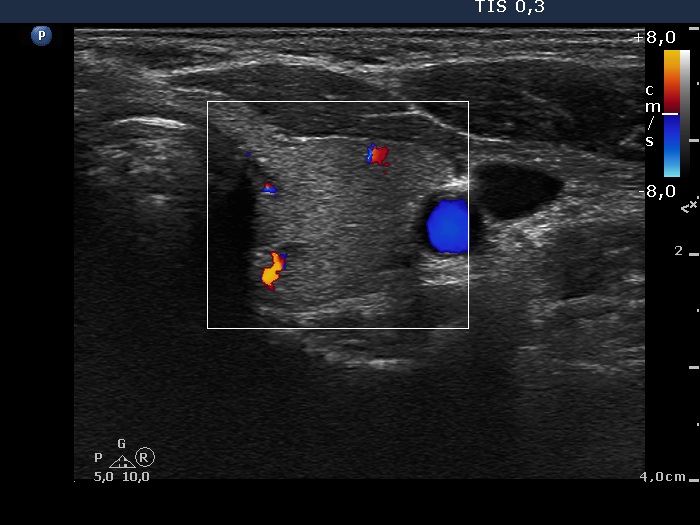

Follow-up 2 months after the first visit (3rd row of images):

Clinical presentation: Within 24 hours of the administration of 32 mg methylprednisolone, the neck complaints and subfebrility had stopped. When the patient reduced the dose to 8 mg daily for 2 weeks as suggested, the left lobe became sensitive. This tenderness has now been significantly reduced, but still persisted at times.

Palpation: The left lobe was tender on palpation.

Laboratory tests: TSH 1.62 mIU/L, FT4 9.97 pM/L, CRP 0.1 mg/L.

Ultrasonography: The right lobe decreased in size as did the extent of hypoechogenic areas in this lobe. The left lobe remained unchanged.

Suggestion: Discontinuation of steroid therapy. TSH in three months.